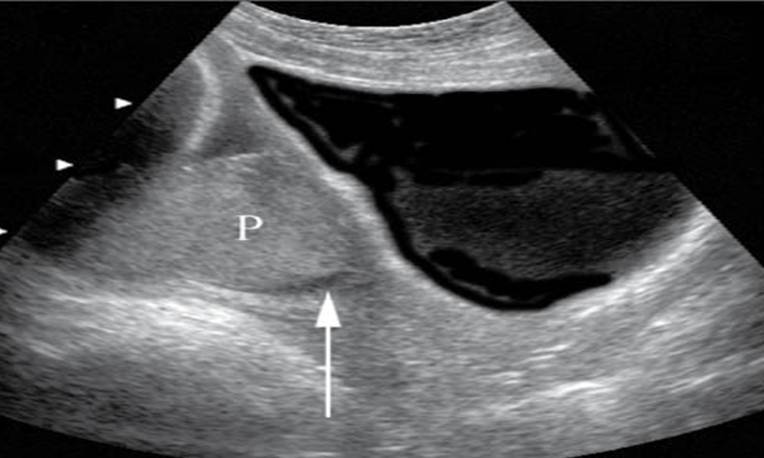

Placenta previa